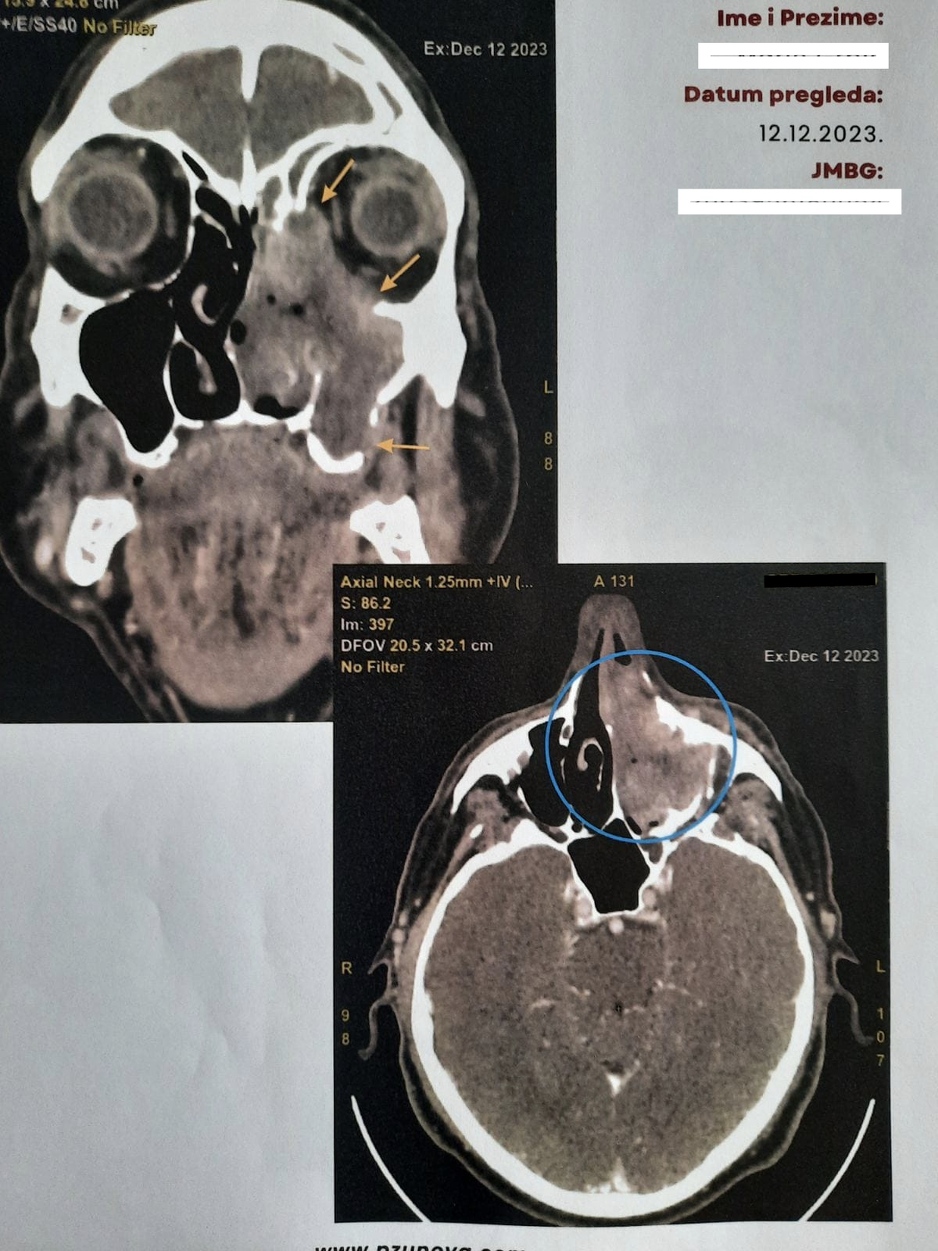

CT glave s karcinom koji je zahvatio lijevu polovinu lica uz destrukciju koštanih struktura